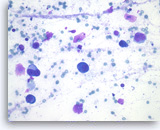

Plasma cell neoplasm,

Pancreas FNA, Direct Smear.

The tumor cells have eccentrically located round nuclei with clumped chromatin and small nucleoli.

40X

Plasma cell neoplasm,

Pancreas FNA, Direct Smear.

The tumor cells have eccentrically located round nuclei with clumped chromatin and small nucleoli.

40X

Plasma cell neoplasm,

Pancreas FNA, Cell Block.

Single tumor cells show eccentric nuclei and occasional binucleation. Flow cytometry demonstrate CD38 positive B-cells without surface immunoglobulin expression. The cytomorphologic features along with flow cytometry results are consistent with plasma cell neoplasm. CD138 immunostain can be performed on the cell block section to support the diagnosis if needed.

40X

Plasma cell neoplasm,

Pancreas FNA, Cell Block.

Single tumor cells show eccentric nuclei and occasional binucleation. Flow cytometry demonstrate CD38 positive B-cells without surface immunoglobulin expression. The cytomorphologic features along with flow cytometry results are consistent with plasma cell neoplasm. CD138 immunostain can be performed on the cell block section to support the diagnosis if needed.

40X